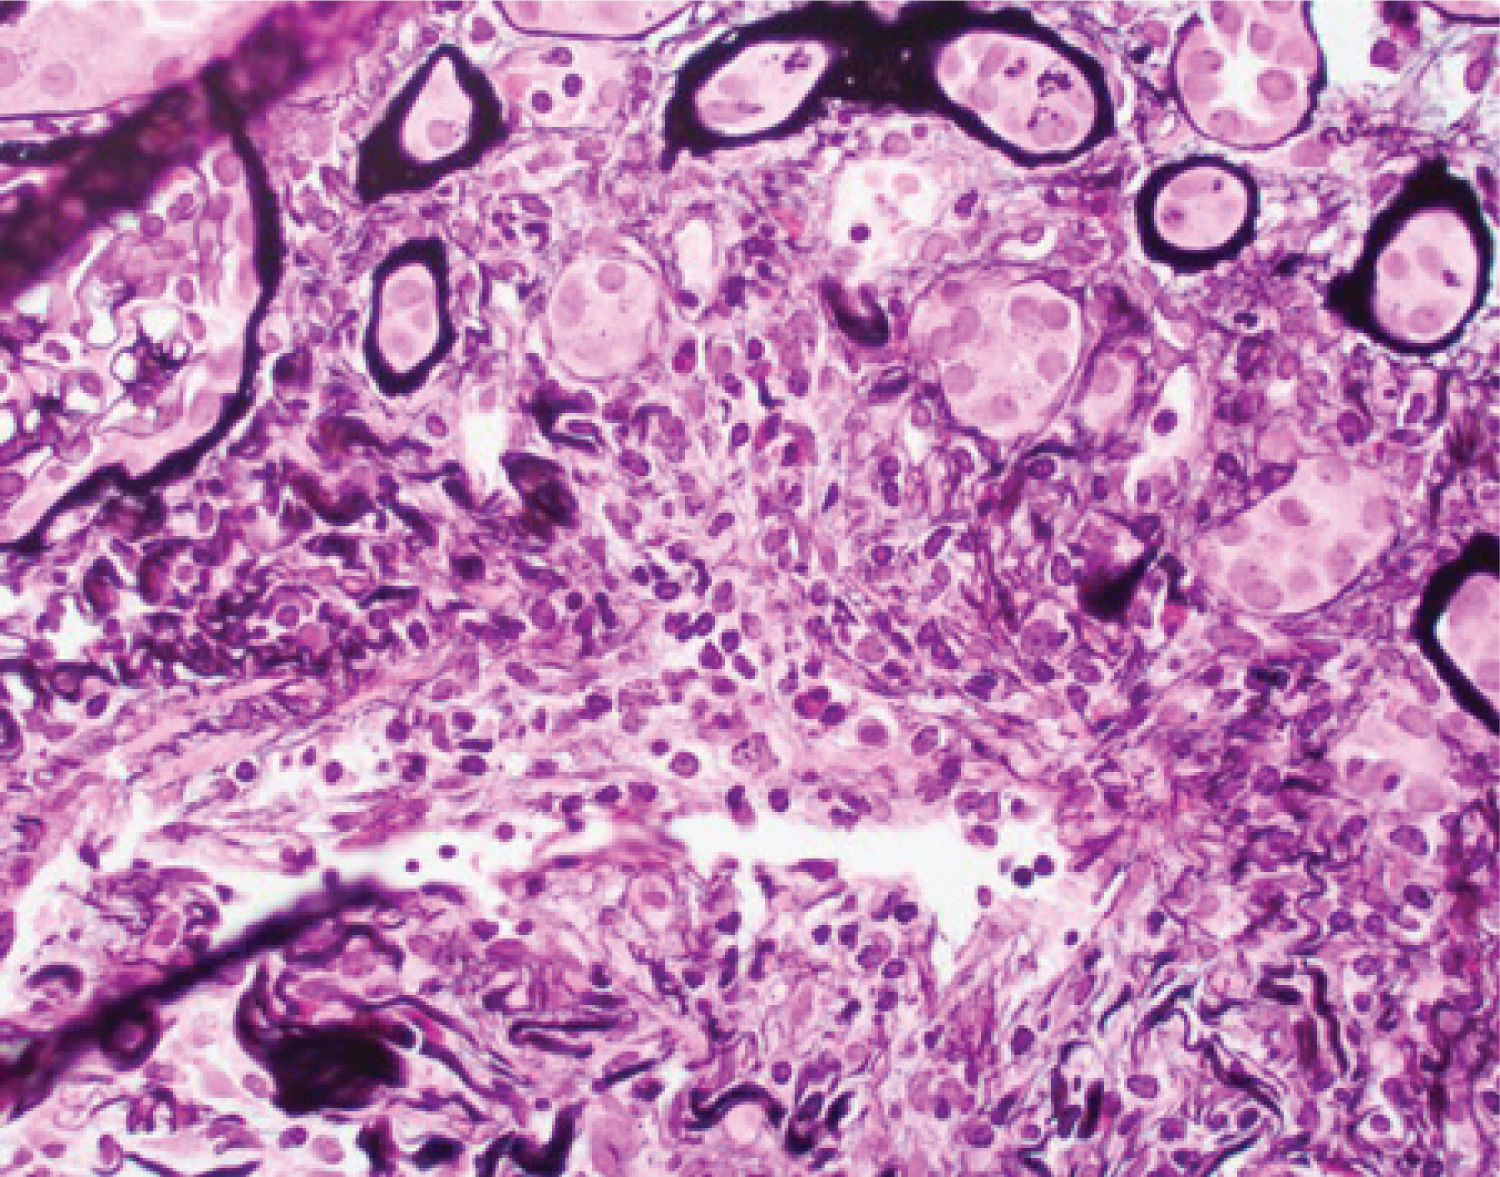

There are several mechanisms by which Cocaine can cause acute kidney injury. These include Rhabdomyolysis, Vasculitis, Platelet activation, Prostaglandin pathways, Oxidative stress [4]. Rhabdomyolysis has been thought to be caused by direct toxicity of cocaine leading to acute skeletal myofibrillar degeneration, vasoconstriction leading to muscle ischemia and necrosis, seizure or hyperpyrexia [5]. In our case outlined above, the patient did admit to having used cocaine and the positive finding of elevated CPK levels which were responding to fluids showed a possible underlying rhabdomyolysis. Although his CPK levels normalized his creatinine continued to trend upwards triggering the need for a renal biopsy. The biopsy did not show any myoglobin deposits but did show some focal vasculitis (Figure 1). Vasculitis in Cocaine abusers has often been attributed to Levamisole. Levamisole was introduced as an anti-helminthic agent which was later withdrawn due to its side effects of liver toxicity, gastrointestinal distress, vasculitic purpura, necrosis of the ears, agranulocytosis and vasculitis. However incidences of Levamisole induced toxicity have been on the rise in cocaine users in the recent past. Levamisole has been added to cocaine to help enhance its euphoric effects. Levamisole increases the Dopamine D1 receptors and has a cholinergic action thus enhancing the effect of cocaine. With a half-life about 5.6 hours, testing for levamisole is quite challenging. Also, specific testing is not readily available at all centers [6]. This may explain a negative urine toxicology screen in our case. We believe that due to lack of any other precipitating factor and negative serologic testing, his renal disease was most likely caused by Levamisole adulterated cocaine (Figure 2).

Figure 2: High-power view of the involved medium-sized artery showing lymphocytic infiltrate in its wall, which also shows partial disruption (Jones silver stain X 400). View Figure 2